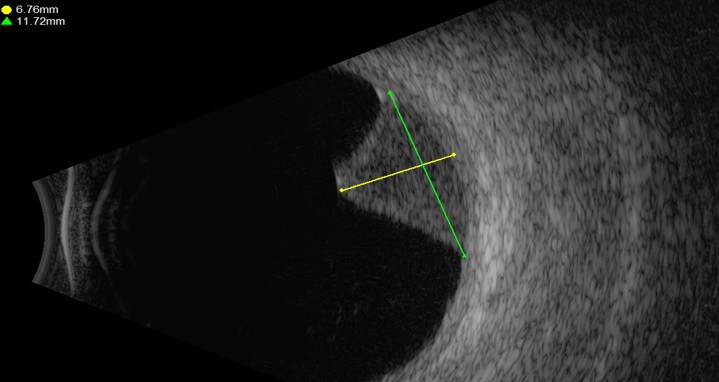

אולטרסאונד של מלנומה בתוך העין

• אולטרה-סאונד עיני (B-scan) – מאפשר לזהות גידולים ולמדוד את עוביים ומיקומם.